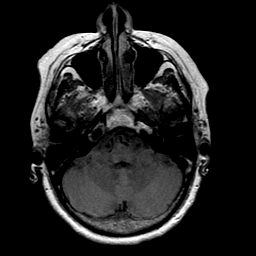

Stroke: proton density-weighted MR #1 -- Slice #5

[Home][Help][Clinical] Slice 5